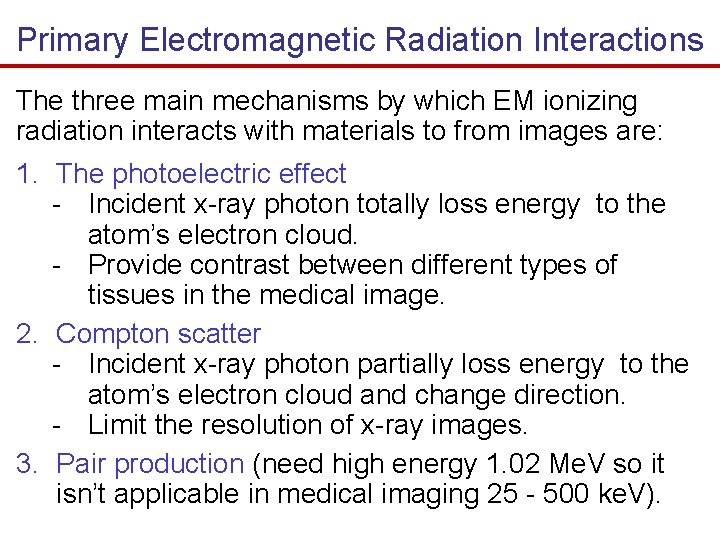

Primary Electromagnetic Radiation Interactions The three main mechanisms by which EM ionizing radiation interacts with materials to from images are: 1. The photoelectric effect - Incident x-ray photon totally loss energy to the atom’s electron cloud. - Provide contrast between different types of tissues in the medical image. 2. Compton scatter - Incident x-ray photon partially loss energy to the atom’s electron cloud and change direction. - Limit the resolution of x-ray images. 3. Pair production (need high energy 1. 02 Me. V so it isn’t applicable in medical imaging 25 - 500 ke. V).